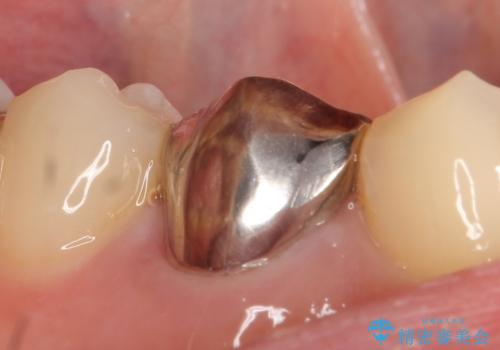

- 右下4番目の歯でものを咬むと疼くような痛みがあるといらっしゃった方の症例です。

X線上で根尖病変を認めたため再根管治療を行い、症状改善後、オールセラミッククラウンによる補綴を行いました。